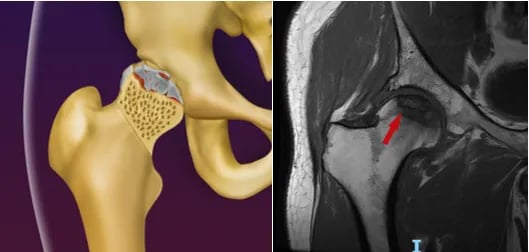

Osteonecrose da cabeça do fêmur

A Osteonecrose da cabeça do fêmur ocorre devido a um defeito na circulação sanguínea para a cabeça do fêmur, levando à morte do osso nessa região, fazendo com que o paciente tenha dor no quadril, muitas vezes acompanhada de dor na coxa.

Essa dor é pior aos movimentos ou ao fazer esforços físicos, muitas vezes limitando o paciente de andar médias distâncias.

Faz-se o diagnóstico com a Ressonância Magnética.

Em relação ao tratamento, não existe uma medicação específica para tal patologia. Casos iniciais, ou seja, em que a esfericidade da cabeça femoral está preservada, o tratamento é feito com uma cirurgia chamada de descompressão ou foragem, na qual remove-se o osso necrótico com uma broca, seguida da colocação de enxerto no local, para estimular a formação de osso normal.

Faz-se o tratamento com a prótese de quadril em casos avançados, ou seja, em que houve colapso/retificação da cabeça femoral ou quando já existe artrose instalada.